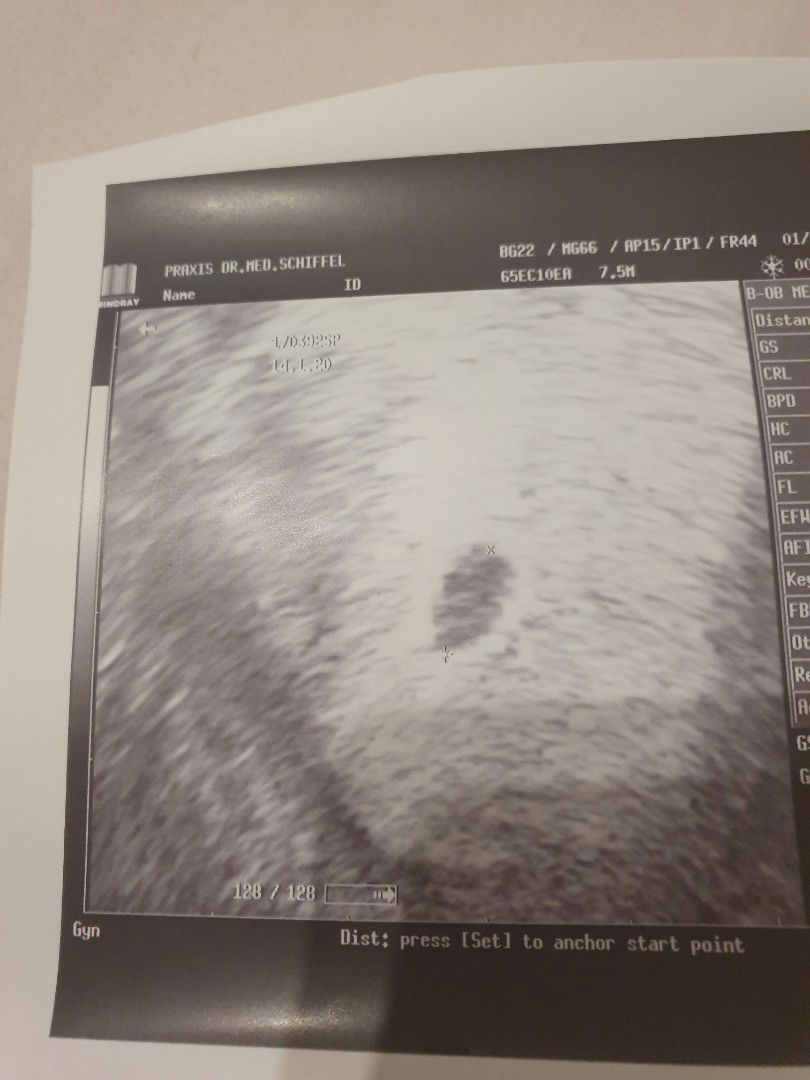

My LMP is 11.24.2019 but the doctor said I am around 5 to 6 weeks only. Is my sonogram normal? Others already have Yolk Sac. Mine ist just empty black circle? Doctor said its fine and will check next week. I worry that there is no Fetus inside ? Update: Jan.22.2020 I was again bu the doctor, the doctor said the size of gestational sac was doubled, last time it was 7.9mm now it is 14.5mm but still no Yolk sac or hearbeat, the doctor scheduled for another UTZ in one week. Has any of you have the same experience? Please enlighten me. Im starting to panic.

I had UTZ is this normal?